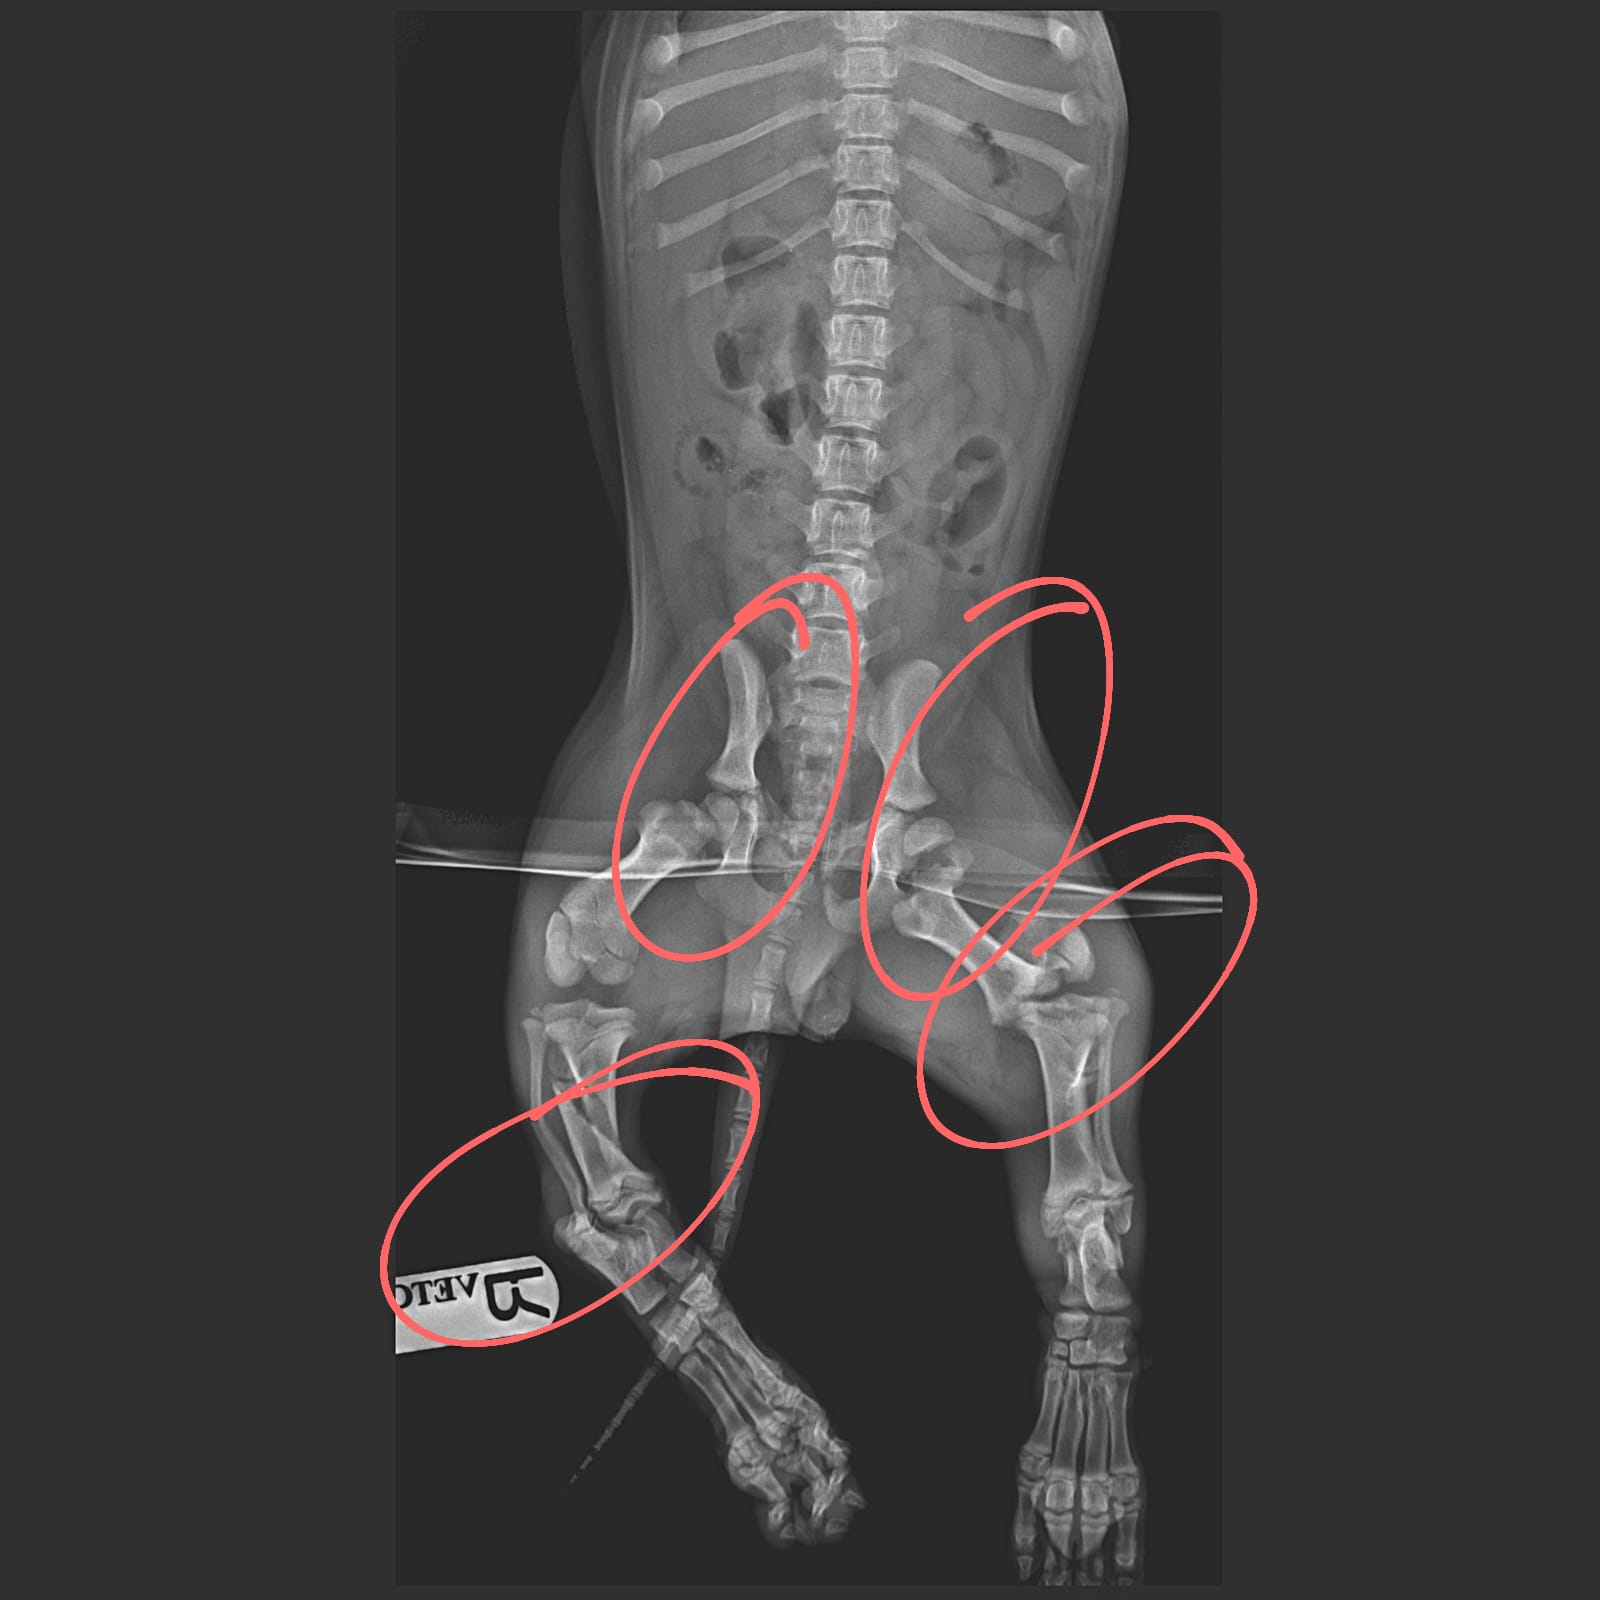

Vor etwas über drei Monaten fand man den kleinen Jungen unter einer Brücke...mit den Vorderläufen robbend schleppte er sich über den Boden...er war schwer verletzt und wie sich in der Tierklinik zeigte waren seine Hinterläufe gebrochen und auch sein kleines Becken hat etwas abbekommen. Vermutlich stürzte er von eben jener Brücke...oder er wurde sogar geworfen (was zum Bild und Art der Verletzungen passen würde)...nur er weiß was geschehen ist...

Er wurde operiert und wieder zusammengeflickt, ganze 3 Monate verbrachte er in der Tierklinik! Das ist die Hälfte seines bisherigen jungen Lebens!

Er wird noch einmal operiert werden müssen, das eingesetzte Metall muss wieder entfernt werden. Und dann, wenn auch das überstanden ist, würde sich der kleine Choco so sehr über seine ganz eigene Familie freuen.